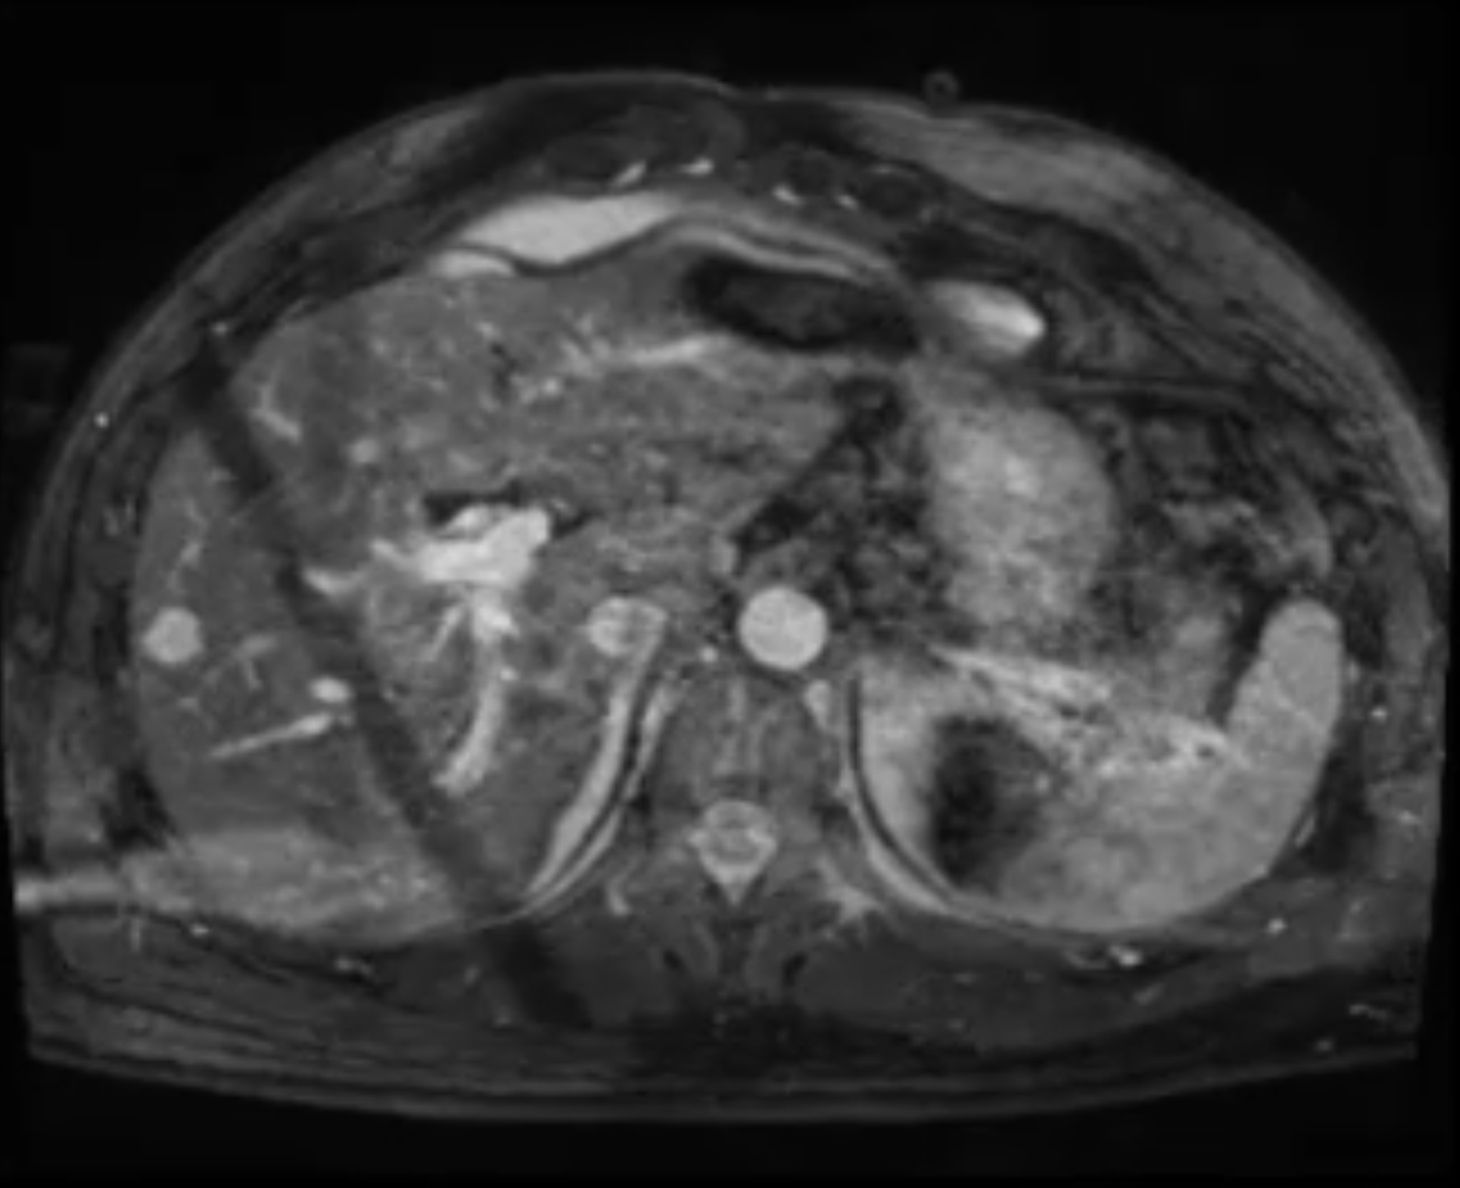

Die kardiale MRT ermöglicht in allen Altersstufen eine hervorragende Darstellung des Herzens und der Gefäße. Sowohl Struktur als auch Funktion lassen sich mithilfe dieser Untersuchungsmethode umfassend beurteilen. So können Fehlbildungen des Herzens und der Gefäße auch bei Säuglingen und Kleinkindern (in Narkose) sehr genau dargestellt werden. Komplexe Herzfehler können den Chirurgen mittels moderner Rekonstruktionstechniken als virtuelles oder reales 3D-Modell zur Verfügung gestellt werden. Zur Anwendung kommen modernste MRT-Scanner (1,5T u. 3T) der Fa. Siemens Healthineers.

Die Kombination der unterschiedlichen MR-Verfahren ermöglicht eine umfassende anatomische Darstellung der Struktur des Herzens und der großen Gefäße:

• Darstellung der Herz- und Klappenfunktion

• Bestimmung von Kammergröße und – volumina

• Darstellung der Herzkranzgefäße

• Messung der Blutversorgung des Herzens

• Stoffwechseluntersuchungen des Herzmuskels